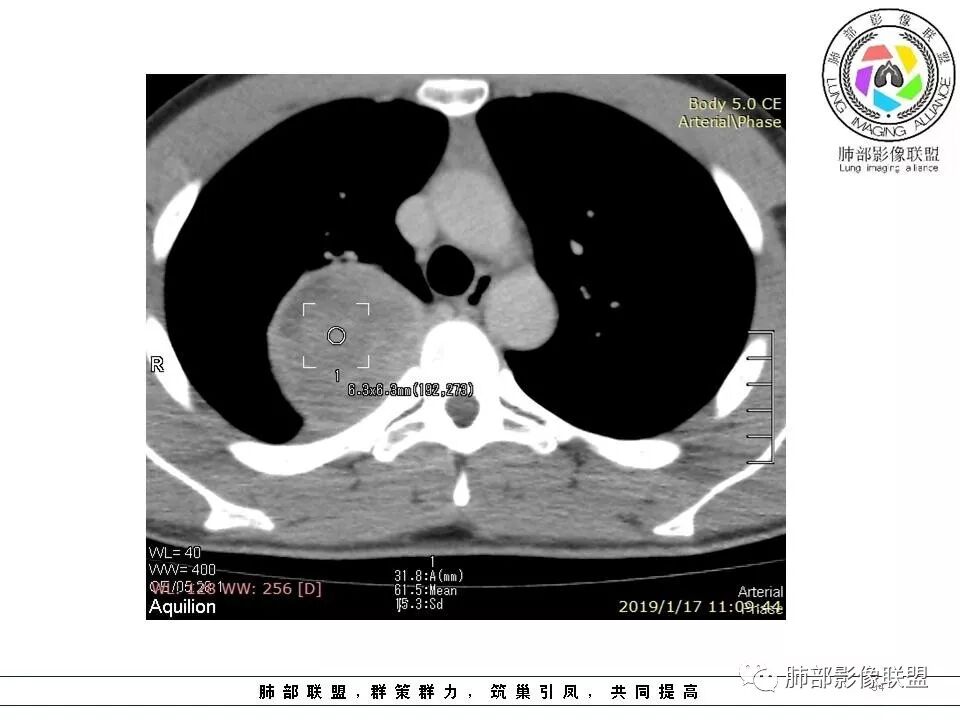

右后纵膈脊柱旁软组织占位,形态规则类圆,边缘光整,肺组织受压,胸膜尾,肋间动脉供血。中度不均匀延迟强化。

后纵隔脊柱旁占位性病变,疾病谱有神经鞘瘤,sft,节细胞瘤,髓外造血。此例有胸膜尾征,蛇纹征 ,延迟强化。考虑胸膜孤立性纤维瘤。看到有供血动脉,但不知道是哪里的血管。

右后纵膈脊柱旁软组织影,与纵隔结构分界不清,形态规则类圆,边缘光整,肺组织受压,胸膜尾,肋间动脉供血。肺动脉推移,中度不均匀延迟强化。考虑神经来源,神经鞘瘤,神经纤维瘤二者不易鉴别。

青年男性,间断胸痛;右侧脊柱旁可见一类圆形软组织密度影,密度欠均匀,增强扫描呈轻中度持续强化,邻近肺组织及肺动脉推移,可见肋间动脉供血,部分胸膜下脂肪可见,部分层面似见与右侧椎间孔相连。考虑后纵隔神经源性肿瘤。

右肺占位,跨越上叶后段、下叶背,边缘光滑,瘤肺界面清,见肺压缩缘(线样不张`强化),见胸膜尾征,胸膜下脂肪未见明显增厚,肋骨丶脊柱未见侵袭及受压,渐进性丶地图样强化,冠状位似见体循环供血

右上肺野脊柱旁软组织肿块,边缘光滑整齐,肺组织及气管右肺上叶支气管受压前移,外移,边缘可见胸膜尾征,病灶内密度不均,增强后渐进性持续强化,其内可见明显蛇纹血管征,首先考虑肺外来源,sft.可能性大

肋间动脉供血,强化尚均匀,逐步强化

1.右上胸内脊柱旁类圆形肿块,质地似乎比较坚实,密度稍显不均,但未显示明确的坏死。

2.肋间动脉病供血也提示肿块来自后纵隔?

4.静脉期轻度不均匀强化,注意不是环形强化,亦未见明确的“AB区”,这点也不支持神经鞘瘤。临床及病灶轻度强化都不支持副节瘤。